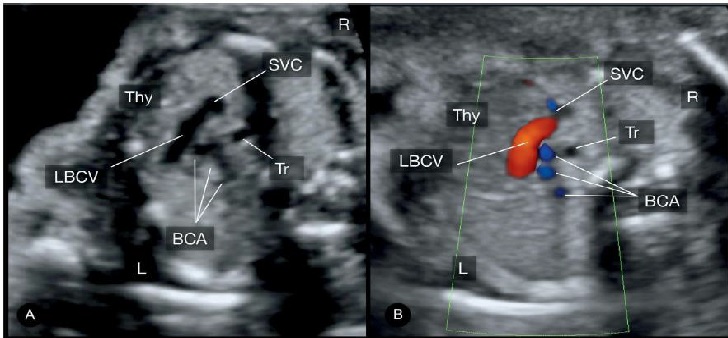

Hình 10: Doppler màu mặt cắt ngang ngực thai nhi ở mức tĩnh mạch cánh tay đầu trái (Left branchiocephalic vein) của thai nhi TAPVR thể trên tim. Hình ảnh thể hiện sự ra tăng lưu lượng máu từ tĩnh mạch phổi. Chú ý Doppler màu (B) thể hiện chiều dòng chảy trong tĩnh mạch cánh tay đầu từ trái qua phải về phía tĩnh mạch chủ trên (SVC). So sánh với tĩnh mạch cánh tay đầu bình thường (Hình.11). Tr: khí quản; L: trái; R: phải.

Hình 11: A & B mặt cắt ngang vị trí trung thất trên, cao hơn so với mặt cắt 3 mạch máu-khí quản. Hình ảnh tĩnh mạch cánh tay đầu trái (left brachiocephalic vein - LBCV). Chú ý vị trí giải phẫu của tĩnh mạch cánh tay đầu trái: Tuyến ức (Thy) ở phía trước và 3 động mạch tay đầu (three brachiocephalic arteries - BCA) ở phía sau. Tr: khí quản; L: trái; R: phải.